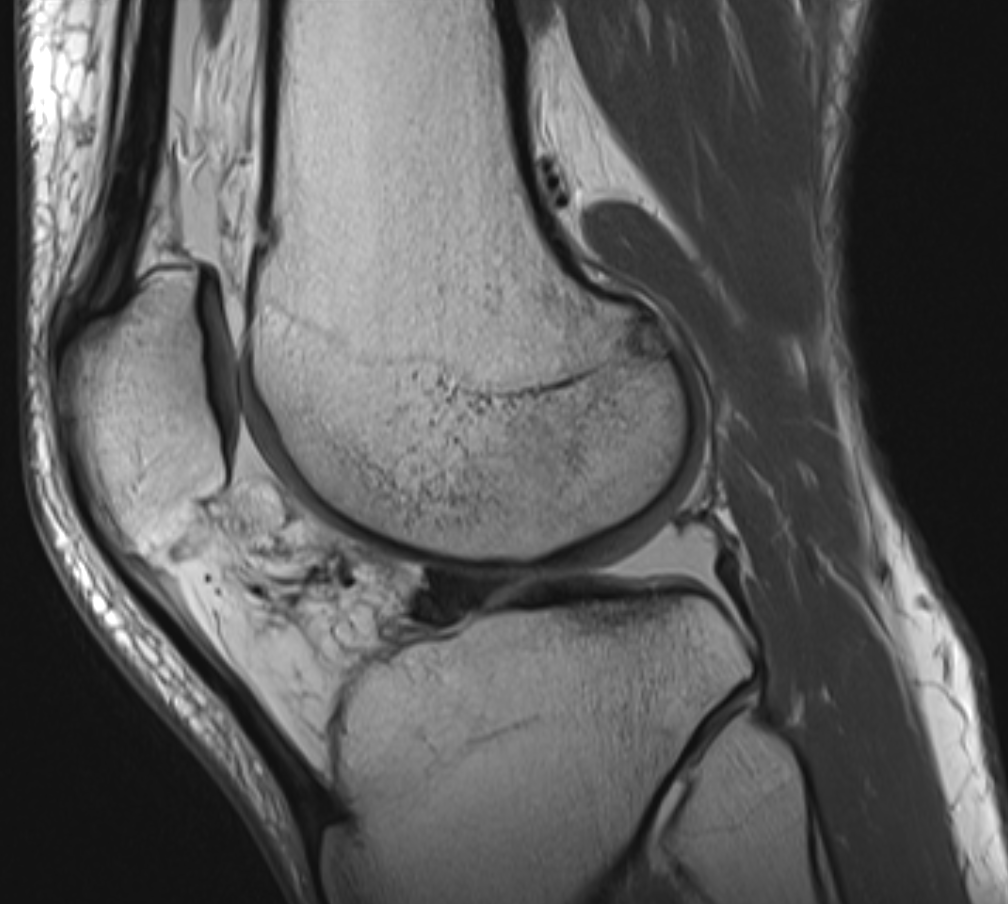

Bucket handle tear of lateral meniscus